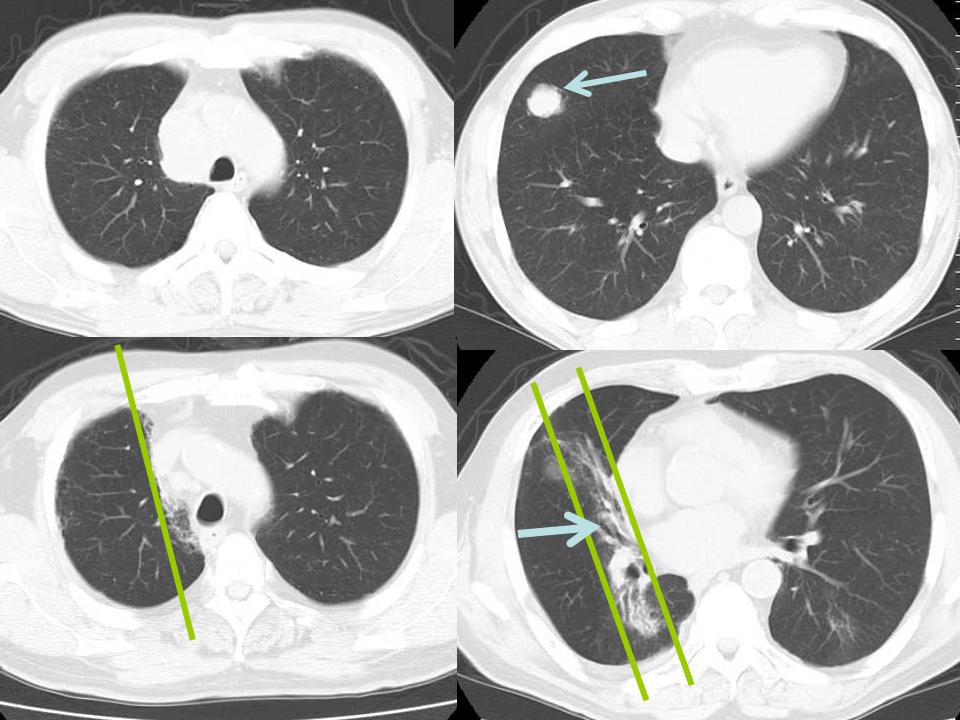

CTで見ると…

3Dだと、こうなります。

気管狭窄ですね。こういう所見もレントゲンで捉えることができるのです。